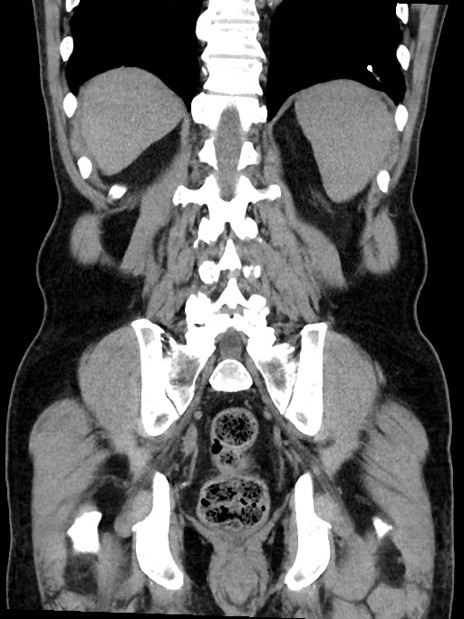

横断像

症例35(冠状断像)

【症例】70歳代 男性

【主訴】腹部膨満、嘔吐

【現病歴】昨日より腹部膨満感出現。本日増悪し、仙痛出現。嘔吐あり、受診。

【既往歴】糖尿病、胆摘後

【身体所見】BP 149/80mmHg、HR 74/min、BT 35.9℃、腹部:膨満、軟、圧痛なし。腸雑音減弱あり。上腹部正中切開瘢痕あり。

【データ】WBC 13500、CRP 1.72